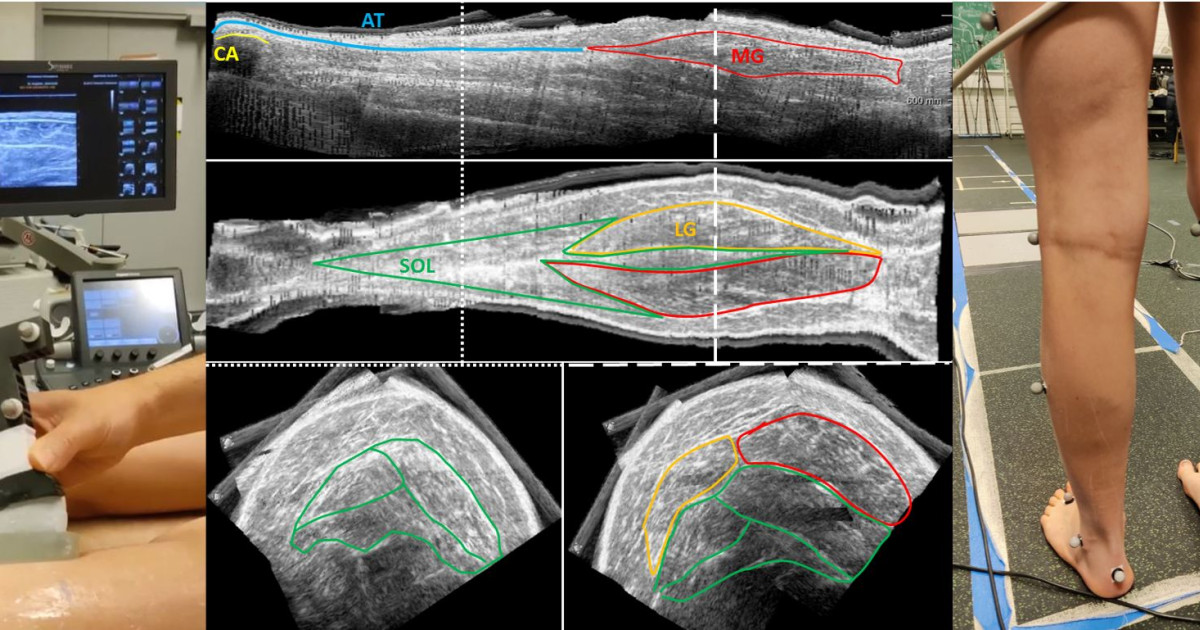

Ankle resistance is also related to the changes in musculoskeletal properties. These changes occur in muscle composition, with fatty infiltration and an increase in the accumulation of connective and fibrous tissues which replace the contractile elements, impeding the muscle to contract functionally. In addition, muscle morphology is altered, including reduced muscle volume and length compared to age-matched typically developing children. Their combination contributes to muscle contractures, increased stiffness (rigidity), and reduced muscle strength. Current methods for analysing morphology, composition, and stiffness are based on magnetic resonance imaging (MRI). MRI technique can be reliably used for estimating intramuscular content. However, an ultrasound (US) approach would be crucial for frequent clinical applications (ideally for monitoring treatments) since it allows low costs and frequent usage. Yet, US methodologies are not yet well established for extracting these parameters. Once the musculoskeletal technique is established, the 3D US framework will be used in JYU for extracting muscle volume, length, and echo-intensity. Children will also participate in 3D gait analysis with simultaneous 2D US imaging. The US probe will be positioned over the medial gastrocnemius (MG) muscle-tendon junction, and over the MG belly allowing imaging of MG and soleus. Since the final goal in cerebral palsy is to improve gait ability, musculoskeletal properties were recently analysed also during walking. However, the relationship between passive and active musculoskeletal properties is still unclear. This relationship will show how altered passive and active musculoskeletal properties affect gait.